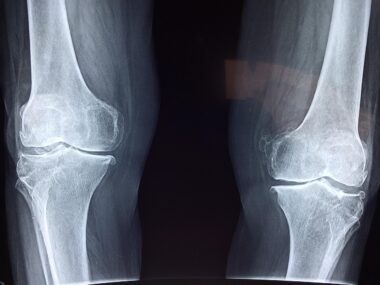

Functional Training Adaptations for Arthritic Joints

Functional training focuses on exercises that improve everyday movements, benefiting those with arthritic joints significantly. By incorporating adaptations specific to the needs of these individuals, functional training can enhance mobility and strength while reducing pain. The main objective is to focus on exercises that mimic daily activities, which allows arthritic patients to regain independence. Exercises should be tailored to the individual’s pain levels and joint restrictions, ensuring that they do not exacerbate the condition. Resistance bands and light weights are excellent tools; they effectively enhance joint stability and improve muscle strength without excessive strain. Additionally, including flexibility and mobility exercises helps maintain joint range of motion and decrease stiffness. Consistent training can lead to improved coordination and proprioception, reducing the risk of falls and injuries. Moreover, it is essential to consult with a healthcare professional or certified trainer when starting a new exercise regimen. They can provide insights into the safest and most effective practices. Incorporating rest and recovery is also crucial, allowing the body to heal while still engaging in regular physical activity. Ultimately, adapted functional training can lead to a more active and happier life for those with joint issues.